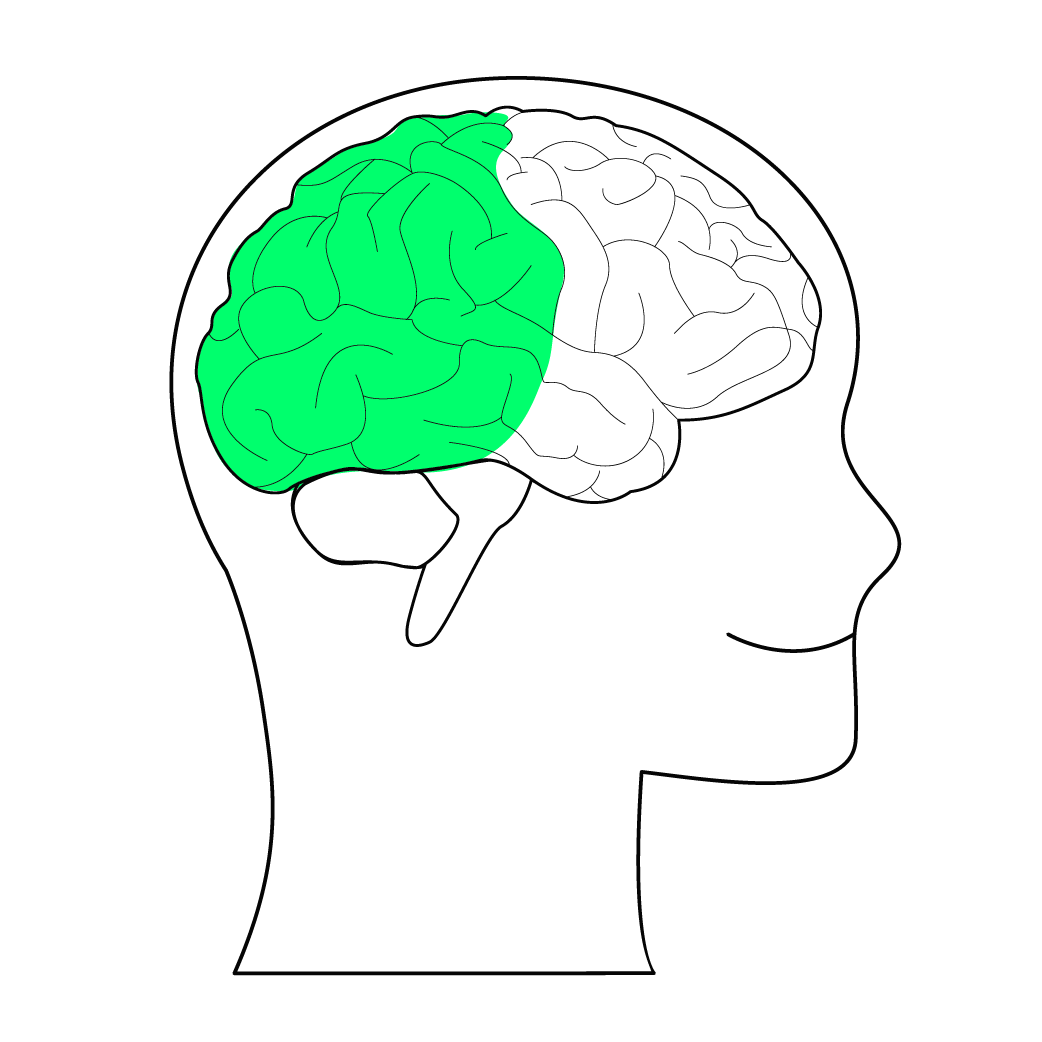

关注生物科学的读者朋友们可能知道,在人体内有两种形式的脂肪组织,一种是储存油脂的白色脂肪组织,脂肪细胞以单颗大油滴的形式储存能量,另一种褐色脂肪组织,细胞内有很多小颗粒油滴和线粒体,是燃脂运动中转化为热量的脂肪。而在这两者之间还有一种游离的“墙头草”脂肪细胞,是一些颜色较深的米色脂肪细胞,它们可以在一定条件下被激活,燃烧能量。

(褐色的脂肪细胞)

而新的治疗思路就是设法让脂肪细胞“褐化”,让它们多耗能、多产热。在这项研究中,科学家们发现,脂肪细胞的褐化有赖于它们制造并降解糖原的能力。具体来说,糖原的这种周转变化会驱动脂肪细胞持续表达一种叫做UCP1(解偶联蛋白1)的蛋白,这个信号告诉细胞,可以安全地“解偶联”ATP分子的生成,从而更快地燃烧能量。

研究人员通过小鼠实验,证实糖原调节并促进了脂肪代谢:糖原的周转程度越高,代谢过程越强,脂肪燃烧速度越快,试验中的肥胖小鼠,体重减轻的效果都很好。科学家们也通过基因检测的方式,从另外的角度证实了这个方式的有效性,科学家们通过基因检测发现在肥胖症患者或是易发胖人群中,这个调节过程涉及的一些基因被发现表达量偏低,说明脂肪细胞中的糖原通路对于燃烧掉多余的脂肪十分必要。

根据这项新发现,针对一些肥胖人群,或许可以靶向脂肪细胞中的糖原代谢。无独有偶,前些日子中山大学医学院杨中汉教授的团队在PLOS Biology上发表最新论文,研究人员发现了促进脂肪燃烧的免疫分子。通过给小鼠注射刺激这种免疫分子后,它们即便大吃大喝也不会肥胖,还能保持代谢健康。而原理类似脂肪细胞的“褐化”,研究人员通过注射特定免疫系统信号分子刺激脂肪细胞,增加脂肪细胞中的“墙头草”米色细胞数量来调节代谢。米色的脂肪细胞中富含线粒体,而线粒体可以大量地消耗能量。

这两个研究都是通过将脂肪细胞“米化”或者是“褐化”来达到调节代谢的目的从而改善代谢。这个思路让我想起了甄嬛传中“皇后杀了皇后”的梗,用脂肪干掉脂肪的思路目前在小鼠实验中都得到了很好的效果,这也是一种从脂肪分子细胞层面治疗肥胖的潜在方案。除了这种相对无痛苦的减脂方案,人类在减肥道路上也有过一些其他的思路。